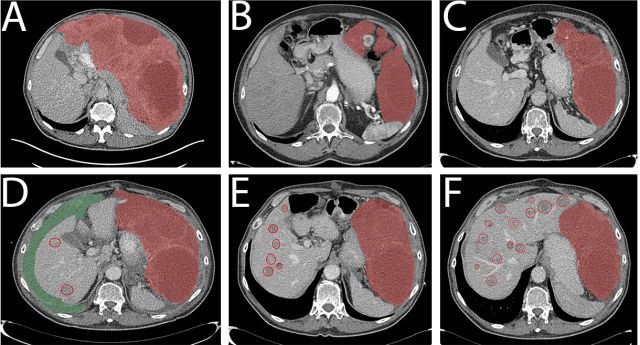

病例1为一个76岁的老年男性,腹部巨大包块(29cm,图1A)),ECOG 3,穿刺证实为GIST,PDGFRα外显子18突变 (NM_006206.5: c.2531_2542del; p.(M844-S847del))。一线给予伊马替尼400mg qd,一周后恶心症状就缓解了,并且生活质量明显改善。治疗持续了1年,最佳疗效为SD(每3月CT评估)。随之腹膜出现了新病灶(图1B),第15个月时调整为二线治疗药物索坦 37.5mg qd。病情在服药后1年内得到良好控制(图1C)。1年后出现PD,中等量腹水(图1D)。经过引流后症状控制,肝脏出现多发转移灶并行穿刺活检,调整为三线药物瑞戈非尼(160mg qd, 3/4方案),PFS为5个月(图1E),并于PD停药后1月死亡(图1F),重头口服伊马替尼无效。患者在三线瑞戈非尼和四线伊马替尼治疗期间留取了血样,发现在1E和1F期间突变拷贝数增加(180-850拷贝/ml,图3A),最后一次随访(死亡前2周)时拷贝数达到4767拷贝/ml。

图1. 病例1的CT图像

病例2为76岁的老年女性,因腹痛就诊,CT发现腹腔25cm的肿块伴多发肝转移(图2A和2B),肝穿刺活检提示CD117阳性GIST,突变分析未发现KIT突变,PDGFRα当时未检测。 一线给予伊马替尼400mg qd,10天后临床症状缓解,耐受性良好,3个月后获得PR(图2C 和2D),30个月后原发肿瘤和肝转移灶都出现了PD(图2E和2F)。重头分析原来标本的PDGFRα发现外显子18突变 (NM_006206.5: c.2527_2538del; p.(I843_ D846del))。患者接受了增量的伊马替尼(400mg BID),耐受性良好,但未获得疗效 (3个月后的CT评估,如图2G和2H)。随后调整为索坦37.5mg qd,但2个月后症状持续恶化,OS总共36个月。 由于组织标本采集困难,本例患者进行了血样的ctDNA分析(图3B) ,结果显示患者在伊马替尼治疗的第16.5个月时突变拷贝为6拷贝/ml,这个低水平一直维持到第30个月。在伊马替尼增量开始时为275拷贝/ml,第33个月增长为852拷贝/ml,索坦治疗启动后,一度降至208拷贝/ml,但因患者在第36个月死亡未再收集血样。

图2. 病例2的CT图像